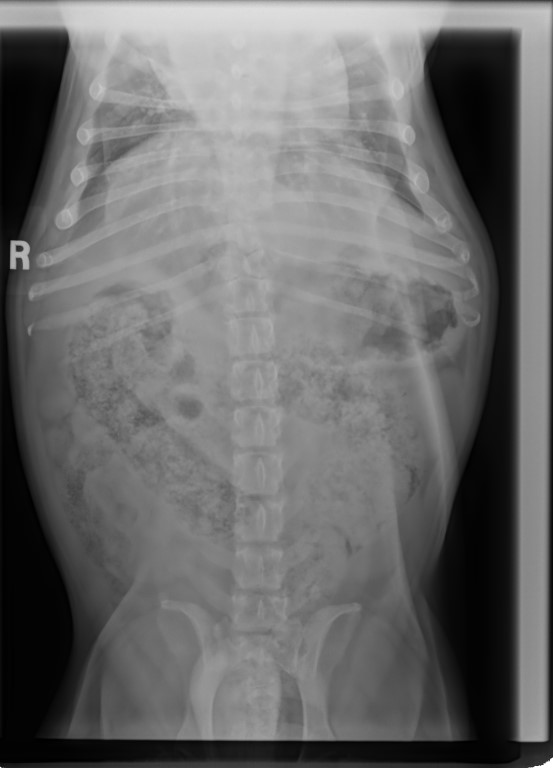

His last nail trim was January 24th before he went to his temp foster home and, he really needs his nails done every 2 weeks yet, with his raw feet, they are too painful. So, all the work we did to get his nails looking great, will just have to see slide a bit for now.

I took him to KAH as I wanted to get an updated weight on him for he had dropped down to 19 kgs and, he was back up to 20 kgs, so giving him the extra 1.5 cups daily as his body fought these infections etc., has helped. He was 20.2 kgs the day he went to his temp foster home.

I cannot stress enough about how I want to see him between 19.8 kgs and 20.5 kgs. He is not to become obese and, of course, we do not want him skinny. Lean and healthy! He is so fit and, looking like a Bulldog should, not what people' 'think' bulldogs should look like – rotund with stomachs protuding.